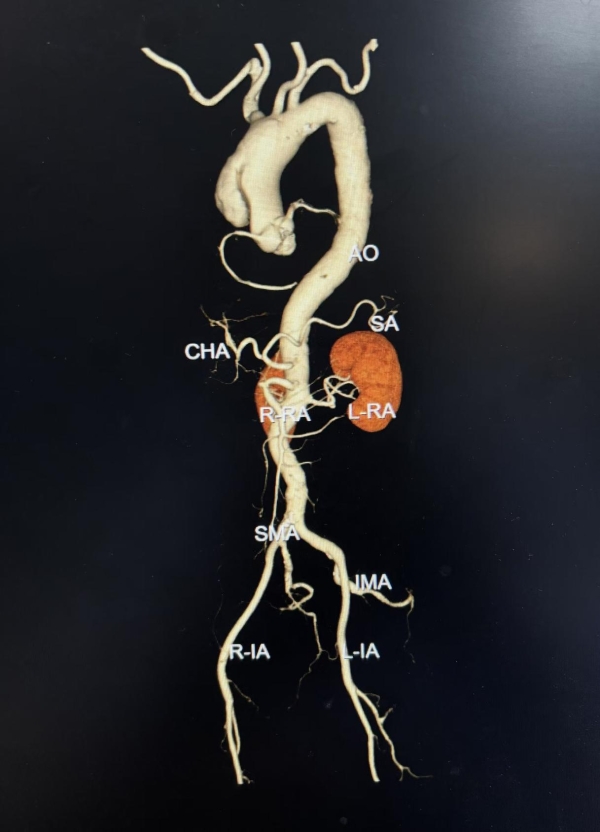

52岁的刘先生,因“突发胸痛2小时”就诊于外院,诊断为急性主动脉夹层(Stanford A型),累及无名动脉、左颈总动脉、左锁骨下动脉等多个分支血管,病情及其危重,需要立即急诊手术。由于该病情重、手术难度大、手术风险极高,对手术医生技术要求非常高,能做该类手术的医院屈指可数。当地医院不能开展如此高难度的顶级手术,建议立即转院,遂慕名来到交大二附院心血管病院急诊就诊。病情紧急,时间就是生命,高峰主任第一时间组织多学科会诊,并开通紧急绿色救治通道,仅用一个小时即完成了术前准备,成功为患者实施了高难度的深低温停循环下主动脉窦部成形+升主动脉、主动脉全弓置换+术中象鼻支架植入术,帮助患者重建生命通道。整个手术犹如刀尖上的舞蹈,开胸、游离血管、建体外循环、切除病变血管、置换人工血管、吻合、植入支架,每一步都小心翼翼。凭借过硬的技术水平和手术团队的密切配合,历经7个多小时,顺利拆除患者体内的“定时炸弹”,使患者转危为安。